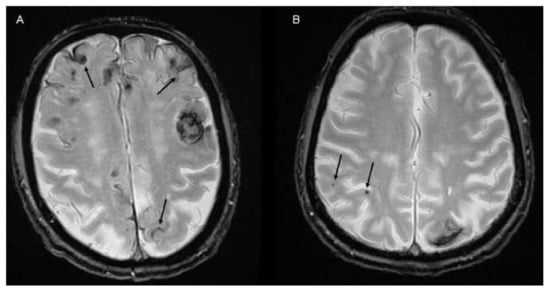

2. Imaging to Identify ICH Etiology

2.1. CTA and DSA for Macrovascular Causes

2.2. Value of CT-Perfusion

2.3. MRI